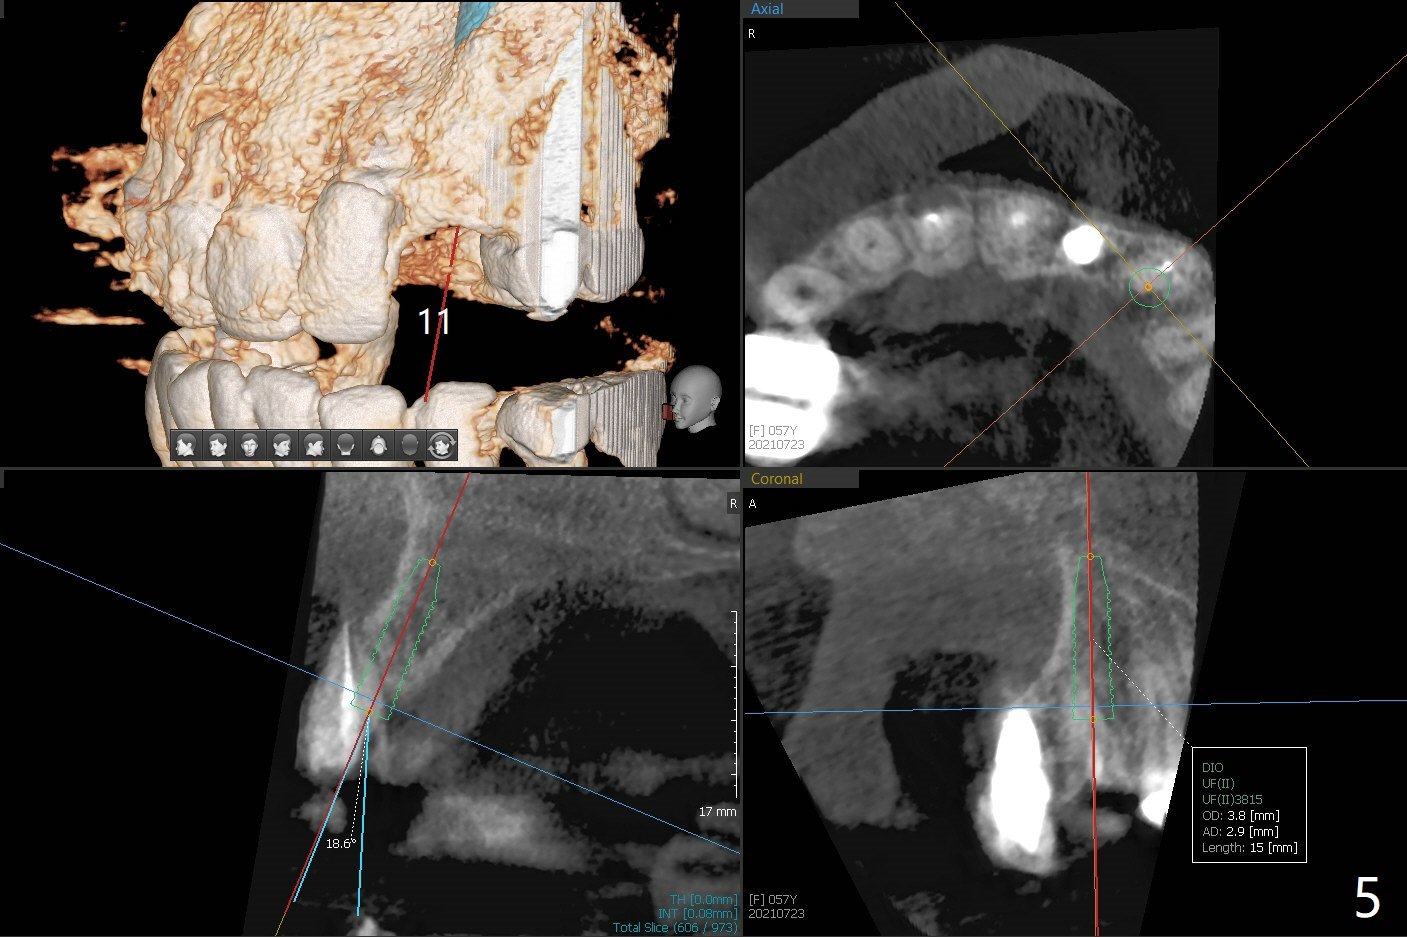

A 57-year-old woman presented to office with dislodged canine crown 10 months earlier (Fig.1). It was cemented. It dislodged again lately. She decides to have an implant and mentions looseness of the implant crown of the lateral incisor. Gingival recession is severe at #10 (Fig.2), while #11 has subgingival fracture (Fig.3). The recession is related to suboptimal angulation and buccal placement of the fixture (Fig.4), while the implant at #11 will be narrow and be placed with sufficient remaining buccal and palatal bone (Fig.5). Socket shield may be done. Prepare gingival retractors. In fact socket shield is not done because of caries in the root stump.